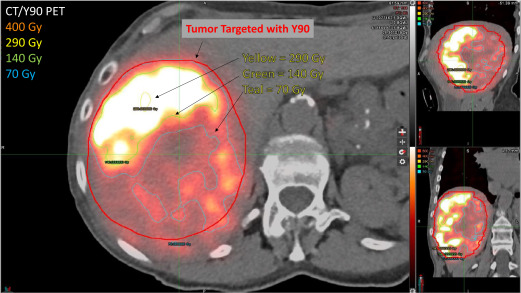

Dosimetry based on 99mTc-macroaggregated albumin SPECT/CT accurately predicts tumor response and survival in hepatocellular carcinoma patients treated with 90Y-loaded glass microspheres: preliminary results.

J Nucl Med. 53: 255-263Salem R. Johnson G.E. Kim E. et al.

Yttrium-90 Radioembolization for the Treatment of Solitary, Unresectable HCC: The LEGACY Study.

Hepatology. 74: 2342-2352Lewandowski R.J. Gabr A. Abouchaleh N. et al.

Radiation Segmentectomy: Potential Curative Therapy for Early Hepatocellular Carcinoma.

Radiology. 287: 1050-1058Vouche M. Habib A. Ward T.J. et al.

Unresectable solitary hepatocellular carcinoma not amenable to radiofrequency ablation: multicenter radiology-pathology correlation and survival of radiation segmentectomy.

Hepatology. 60: 192-201Riaz A. Gates V.L. Atassi B. et al.

Radiation segmentectomy: a novel approach to increase safety and efficacy of radioembolization.

Int J Radiat Oncol Biol Phys. 79: 163-171Biederman D.M. Titano J.J. Korff R.A. et al.

Radiation Segmentectomy versus Selective Chemoembolization in the Treatment of Early-Stage Hepatocellular Carcinoma.

J Vasc Interv Radiol. 29: 30-37.e2Padia S.A. Johnson G.E. Horton K.J. et al.

Segmental Yttrium-90 Radioembolization versus Segmental Chemoembolization for Localized Hepatocellular Carcinoma: Results of a Single-Center, Retrospective, Propensity Score-Matched Study.

J Vasc Interv Radiol. 28: 777-785.e1Dewaraja Y.K. Chun S.Y. Srinivasa R.N. et al.

Improved quantitative.

Med Phys. 44: 6364-6376Garin E. Tselikas L. Guiu B. et al.

Personalised versus standard dosimetry approach of selective internal radiation therapy in patients with locally advanced hepatocellular carcinoma (DOSISPHERE-01): a randomised, multicentre, open-label phase 2 trial.

Lancet Gastroenterol Hepatol. 6: 17-29Kappadath S.C. Mikell J. Balagopal A. et al.

Hepatocellular Carcinoma Tumor Dose Response After.

Int J Radiat Oncol Biol Phys. 102: 451-461Wei L. Cui C. Xu J. et al.

Tumor response prediction in.